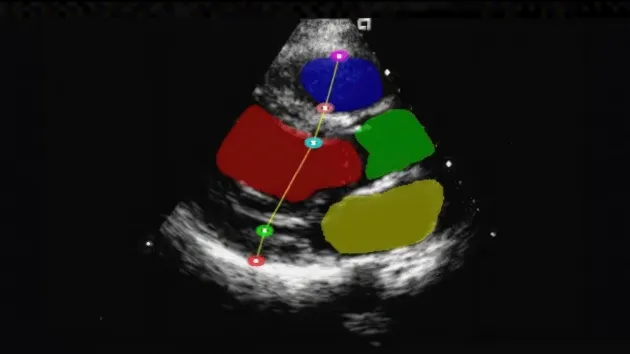

NVIDIA Clara™ for Medical Devices processes streaming data in real time with scalable, software-defined devices built with the NVIDIA Clara platform. It provides an accelerated, full-stack infrastructure that enables real-time AI processing, seamless sensor integration, and rapid development of medical solutions at the clinical edge.

- Real-Time AI Processing: Build real-time AI applications at the clinical edge with NVIDIA Holoscan.

- Seamless Sensor Integration: Integrate sensors seamlessly for real-time data processing.